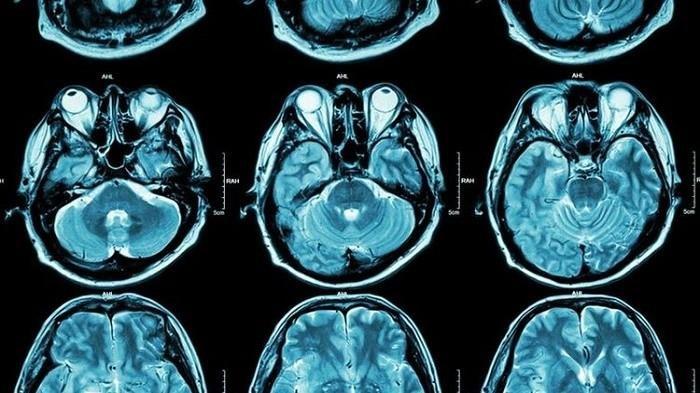

Penyakit Mematikan, Waspada 8 Gejala Awal Tumor Otak yang Perlu Diketahui

Awas, 8 gejala awal tumor otak yang perlu diketahui, Tumor otak yang bersifat nonkanker dikenal sebagai tumor otak jinak.

TRIBUNNEWSWIKICOM - Tumor otak adalah salah satu penyakit mematikan.

Penyakit ini terjadi dimana ada pertumbuhan sel tidak normal di otak.

Dilansir dari Mayo Clinic, tumor otak ada yang jinak sampai ganas.

Tumor otak yang bersifat nonkanker dikenal sebagai tumor otak jinak.

Sedangkan tumor otak yang bersifat kanker dikenal sebagai tumor otak ganas.

Tingkat keganasan tumor otak memengaruhi cepat atau lambatnya pertumbuhan tumor.

Begitu massa tumor tumbuh membesar dan menyerang satu lokasi tertentu, gejala penyakit mulai muncul karena sistem saraf turut terganggu.